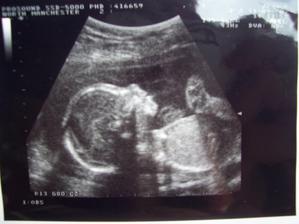

Nase miminko Isabella :o)

Tak se nam konecne splnil sen a 7.2.2008 se nam narodila zdrava a krasna princezna Isabella vazila 3.740kg a merila 54cm, je to kus baby :o) . Je to nas nejhodnejsi milacek a nejradsi bysme ji upusinkovali k smrti :o))) !!!!!

No a kdyz jsem mela 3 tydny tak se ukazalo ze nejsem zase az tak zdrava, stravila jsem 3 mesice v nemocnici s moji maminkou, z toho skoro mesic na JIP. Domu jsme sli na infuzich a maminka s tatinkem mi je zavadeli kazdy vecer na noc a rano pichali leky ...Doktori rikali ze budu v 11 mesicich potrebovat transplantaci kostni drene a same horsi veci, ale po 4 mesicich takove pece co mi rodice doma davali jsem ted snad skoro zdrava, jenom na jednich lekach, mam sice velkou dietu, ale to nevadi... Hlavne ze uz zadne jehly aspol.. A snad uz se to nikdy nevrati....